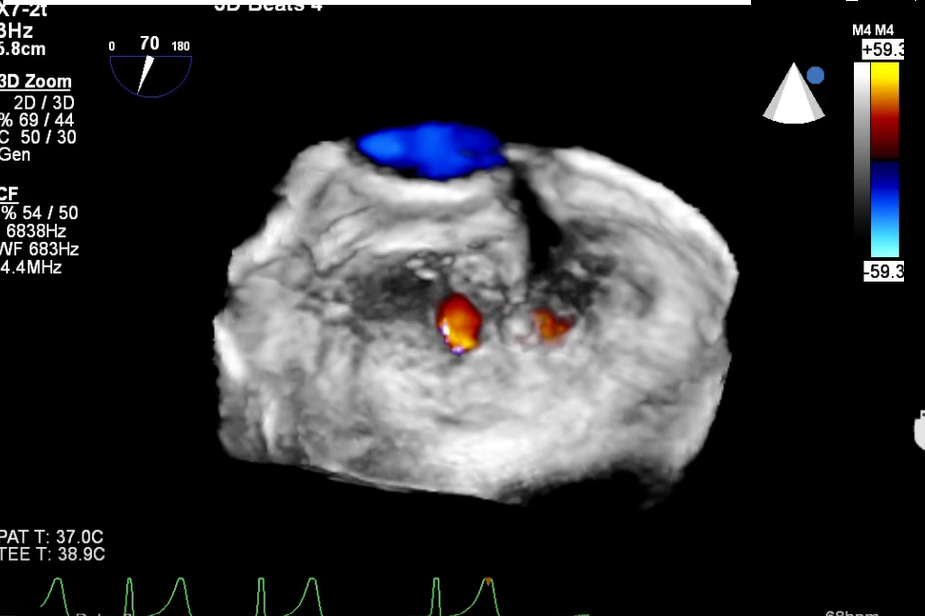

术前TEE显示二尖瓣重度反流,确认二尖瓣后瓣(P2)脱垂

A2区前叶长度23.3mm,后叶长度15.3mm,连迦宽度12.7mm,间隙9.5mm,反流口面积0.75cm²,有效瓣口面积5.64cm²。

二尖瓣重度关闭不全,考虑DMR。